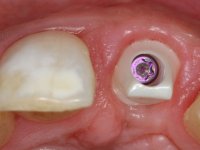

Os cotos de óxido de zircónio são dos assuntos mais debatidos em implantologia. A sua resistência à fractura, as conexões externas e internas, a interacção entre o parafuso de retenção e o coto – todos estes assuntos são abordados repetidamente. No entanto, todos parecem concordar que os cotos de óxido de zircónio apresentam resultados altamente previsíveis, especialmente na restauração de dentes anteriores. Outro argumento em favor dos cotos de óxido de zircónio é a alta biocompatibilidade do material.

A comparação entre o óxido de zircónio e o dissilicato de lítio mostra que o último pode sofrer ataque ácido e ser silanizado e assim ser preparado para uma cimentação adesiva. Uma dica: no sentido de criar no coto de óxido de zircónio uma superfície susceptível de ser gravada pelo ácido, a superfície a ser colada pode ser recoberta com uma fina camada de cerâmica de adesão antes de modelar a coroa. Para este propósito, a ceram Zirliner é aplicada primeiro, depois aplica-se uma camada de ceram de dentina profunda na tonalidade desejada. Como resultado, a cor da dentina ilumina a restauração a partir do seu interior e cria a possibilidade de ser aplicado um protocolo de cimentação adesiva.

A confecção de um coto de óxido de zircónio com uma coroa de cerâmica vítrea prensada de dissilicato de lítio mimetizou perfeitamente os dentes vizinhos.